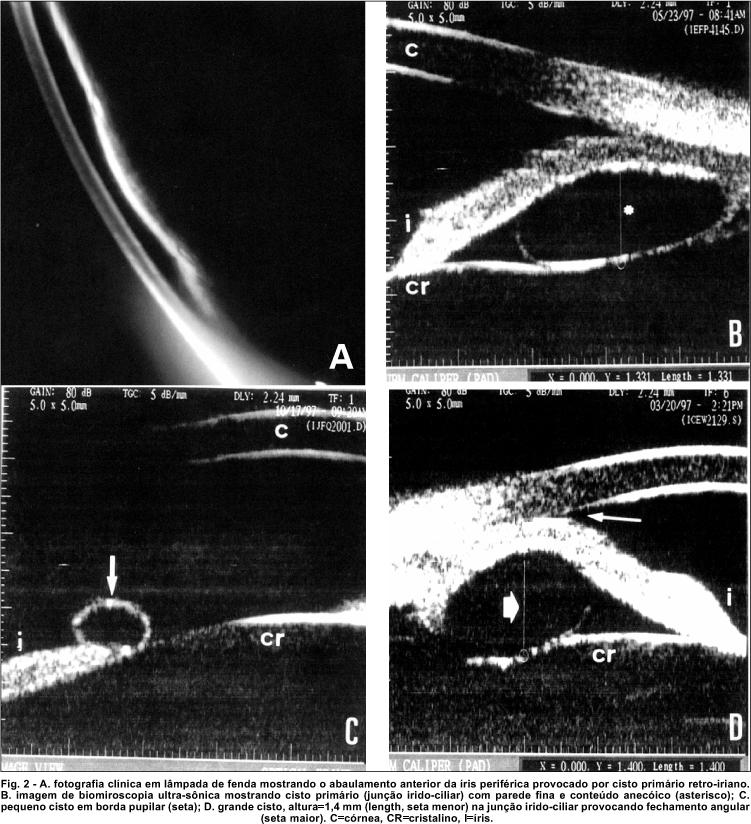

Ao exame de UBM, os cistos primários de epitélio pigmentar de íris e corpo ciliar caracterizaram-se por apresentarem uma parede fina, regular, lisa, de média refletividade com conteúdo anecóico (figura 2).

O estudo do ângulo camerular revelou 40 pacientes com ângulo aberto e 40 pacientes com estreitamento e/ou fechamento focal (figura 2d), ou seja, correspondente à topografia do cisto. Não ocorreu diferença significante entre as incidências (p>0,05, correção de Yates). Foram observados 2 casos (2,4%) de fechamento de ângulo por 360o, não relacionado à topografia dos cistos.

Ao exame de UBM, os cistos primários de epitélio pigmentar de íris e corpo ciliar caracterizam-se por apresentarem uma parede fina, regular, lisa, de média refletividade e conteúdo anecóico. Prévios estudos demonstraram que o número de cistos primários periféricos de íris detectados ao exame com UBM é maior do que o esperado aos exames clínicos convencionais 9.